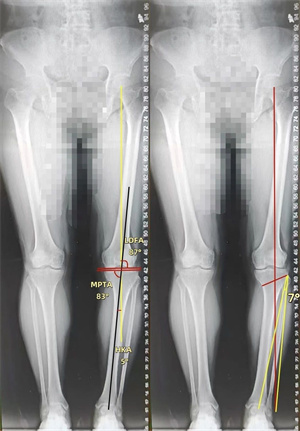

手术团队通过 X 线、CT 等影像学评估,精确计算出下肢力线偏移角度,确定截骨位置及矫正目标;术中采用开放楔形截骨术(OWHTO),在胫骨近端内侧作小切口,借助导向器完成截骨后,撑开骨间隙植入人工骨材料,并用解剖钢板固定,整个过程出血量不足 50ml,耗时约 1 小时,术后患者下肢力线即刻恢复生理曲度;术后第三天,患者便开始部分负重行走,摄片检查显示下肢力线已纠正,结合股四头肌锻炼、关节活动度训练等个性化康复训练,4 周后逐步过渡至完全负重,膝关节疼痛显著缓解,功能恢复良好。

▷通过双下肢全长片测量下肢力线偏移角度